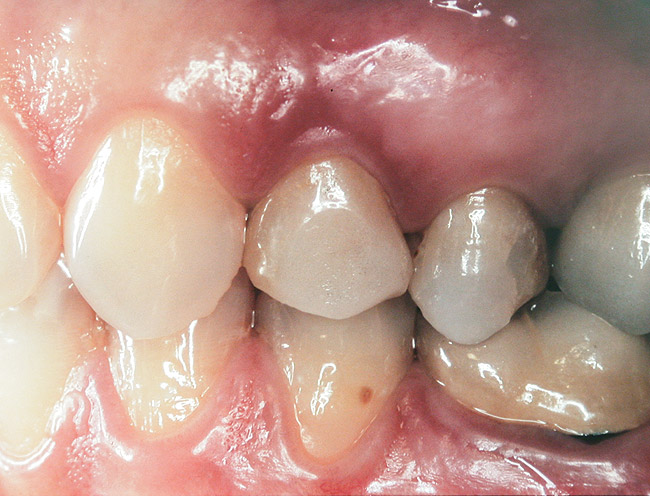

A 45-year-old female was referred for implant placement and prosthetic treatment in the area of tooth No. 24. The tooth had been extracted 4 years prior; the patient did not wear any denture thereafter. The radiograph revealed adequate bone height and a 5-mm to 6-mm ridge at the crest (Figure 2). It was decided to place a 11.5 mm in length, 3.75 mm in diameter Tapered Screw-Vent® implant (Zimmer Dental, www.zimmerdental.com) using the alveolar remodeling technique in the area of tooth No. 24.

At the time of surgery, local infiltrative anesthesia was administered (lidocaine 2% with epinephrine, 1:100,000). A full-thickness mucoperiosteal flap was raised. The initial osteotomy was performed on midcrestal bone using a rose-headed bur. To prepare the osteotomy site for implant placement, sequential alternating osteotomes with variable conicity were used, drilling 2-mm shorter than the length of the implant to be placed (Figure 3A and Figure 3B). The implants presented initial primary stability (Figure 4), the cover screws were placed, and the implants were submerged for a healing period. The tissue was approximated, and the patient was instructed not to wear any denture or to place pressure on the healing site.

Second-stage surgery was performed after 5 months; healing abutments were placed, and the soft tissue was allowed to heal for an additional 5 weeks. Splinted porcelain-fused-to-metal (PFM) crowns supported by custom gold abutments then were delivered (Figure 5).

Figure 3a  Alternating osteotomes with variable conicity used to perform the alveolar remodeling in the area of tooth No. 24.

Figure 3a

Figure 3b  Alternating osteotomes with variable conicity used to perform the alveolar remodeling in the area of tooth No. 24.

Figure 3b

Figure 4  Implant positioning; the radiograph taken 4 weeks after placement confirmed good primary stability.

Figure 4

Figure 5  Final implant-supported PFM restorations.

Figure 5